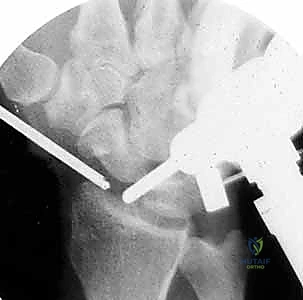

Standard orthogonal plain radiographs (posteroanterior, lateral, and oblique views) of the affected digit are mandatory. These images are utilized to assess the remaining osseous architecture, evaluate for the presence of radiopaque foreign bodies, and identify associated phalangeal fractures that may require concurrent stabilization.

Clinical & Radiographic Imaging